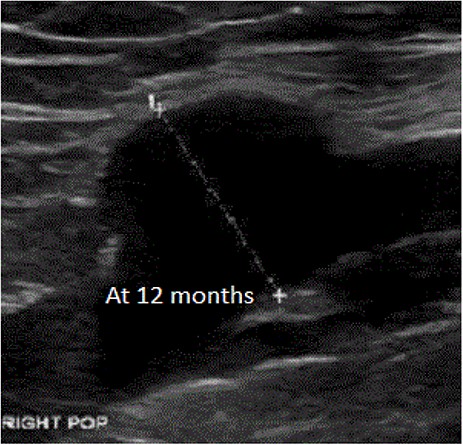

An 81-year-old male with a history of poorly controlled congestive heart failure, chronic obstructive pulmonary disease and atrial fibrillation among other comorbidities was admitted to the hospital for worsening bilateral leg swelling and cellulitis. The patient had an injury to his left medial malleolus 2 weeks prior, which failed outpatient care. During the physical exam, a soft mobile mass was palpated in the right popliteal fossa along with bilateral varicose veins, +1 pitting edema in bilateral lower extremities up to mid-calf. Duplex ultrasound revealed a saccular dilation in the right popliteal vein measuring 2.2 × 1.8 × 2.8 cm, without any evidence of superficial or deep vein thrombosis. After an extended conversation with the patient and his care team, a decision to continue with medical management with close monitoring was made. Follow-up ultrasounds performed at 1, 6 and 12 months show no changes.

An 81-year-old male with a history of poorly controlled congestive heart failure, chronic obstructive pulmonary disease and atrial fibrillation among other comorbidities was admitted to the hospital for worsening bilateral leg swelling and left lower extremity cellulitis. The patient had an injury to his left medial malleolus from an ill-fitting new shoe 2 weeks prior, which had failed outpatient care. During the physical exam, a soft mobile mass was palpated in the right popliteal fossa along with bilateral varicose veins, +1 pitting edema in bilateral lower extremities up to mid-calf. Duplex ultrasound revealed a saccular dilation in the right popliteal vein measuring 2.2 × 1.8 × 2.8 cm (Fig. 1), without any evidence of superficial or deep vein thrombosis (DVT). After an extended conversation with the patient and his care team, a decision to continue with medical management with close monitoring was made. Follow-up ultrasounds performed at 1, 3, 6, 9 and 12 (Fig. 2) months show no changes.